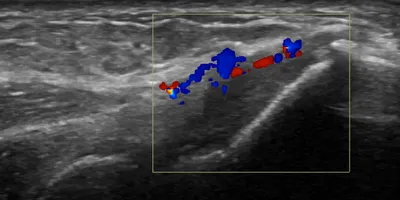

11 imagesCommon extensor enthesopathy (tennis elbow)

Elbow

4/10/2026